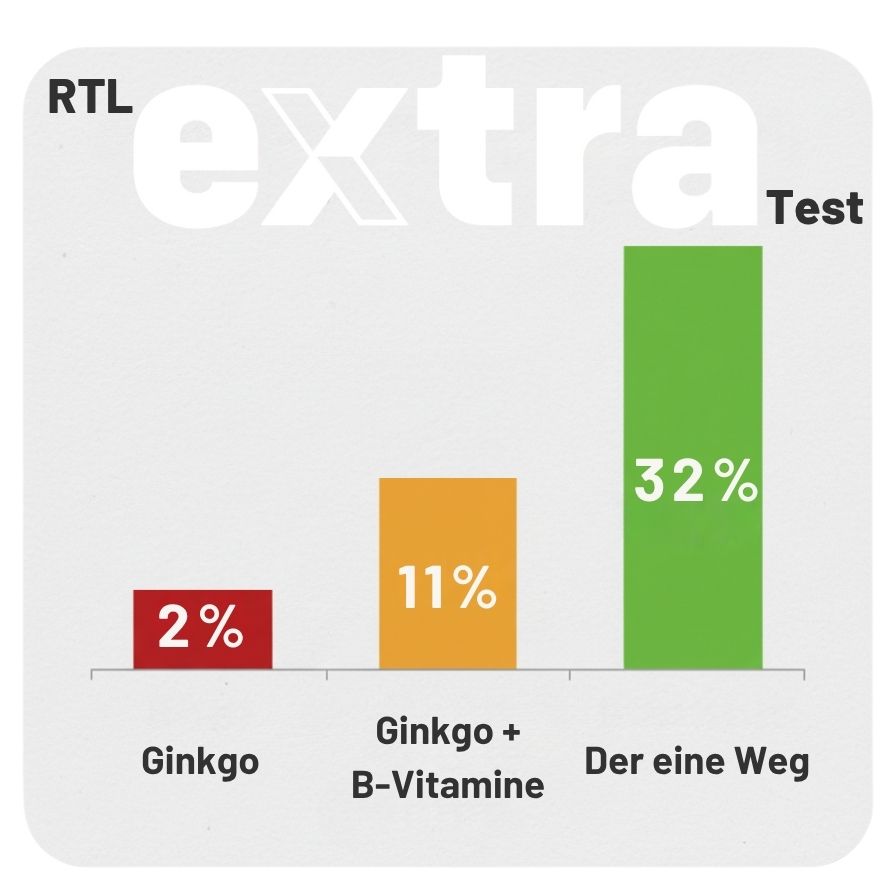

So ändert sich die Gehirnleistung nach 12 Wochen

RTL-Extra testete es an Demenz-Patienten:

Quelle: RTL Extra – Testergebnis zum Vergleich der Wirksamkeit

- Oxford-Universität: „32% weniger Gehirnschwund nach 6 Monaten“